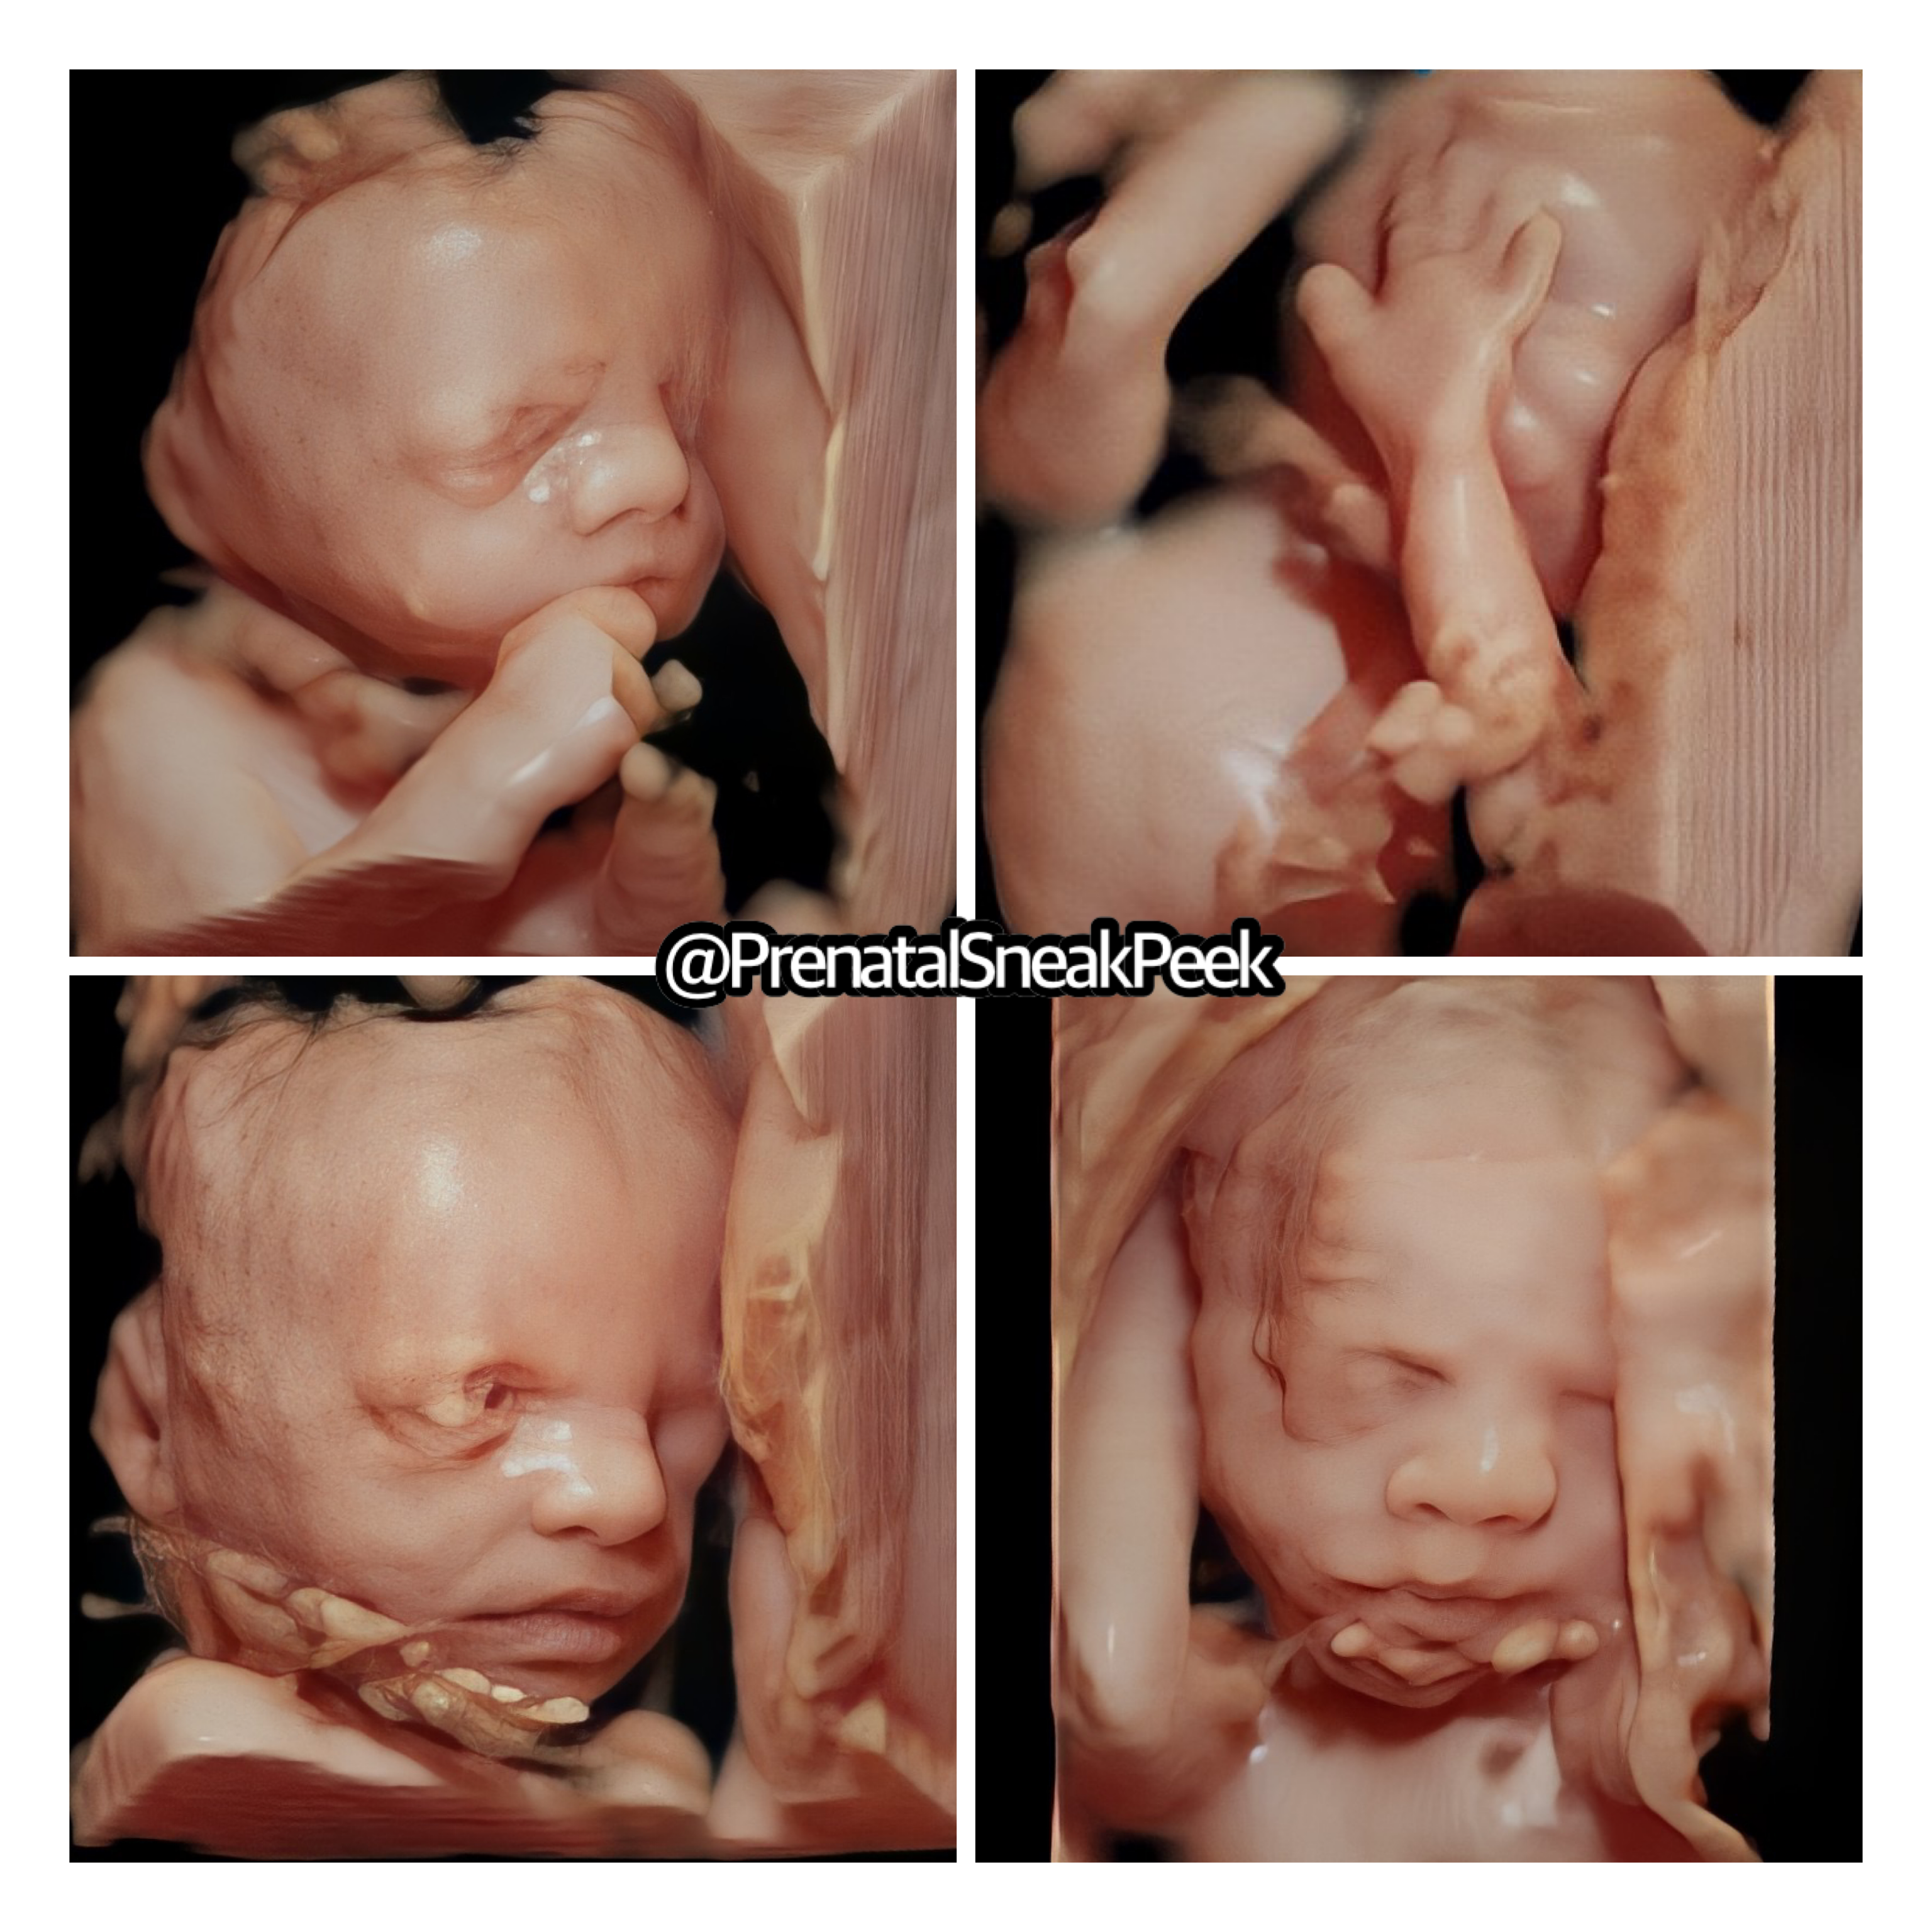

ABOUT PRENATAL SNEAK PEEK

Prenatal Sneak Peek is an elective mobile ultrasound company that provides ultrasounds in the comfort of your home. It is owned and operated out of Bel Air MD. Owner, Kelly Wargo, RDMS is a Registered Diagnostic Medical Sonographer with a specialty certification in OB. She has over 15 yrs. experience in the field of ultrasound. Kelly is the sole operator of her business; therefore, you will get the same quality every time! She also has a heart for saving babies, providing ultrasound services part-time to Options@328 a nonprofit located in Baltimore City.